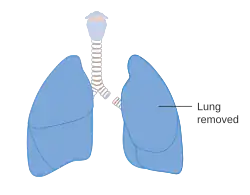

A pneumonectomy (or pneumectomy) is a surgical procedure to remove a lung. It was first successfully performed in 1933 by Dr. Evarts Graham. This is not to be confused with a lobectomy or segmentectomy, which only removes one part of the lung.

There are two types of pneumonectomy: simple and extrapleural. A simple pneumonectomy removes just the lung. An extrapleural pneumonectomy also takes away part of the diaphragm, the parietal pleura, and the pericardium on that side.[1]

Living with one lung

As with the kidneys, it is often possible for a person to live with just one lung. Although it is not possible for the lung to re-grow like the liver, the body is able to compensate for the reduced lung capacity by slow and gradual expansion of the other remaining lung. Post-pneumonectomy patients in due time reach about 70–80 percent of their pre-surgery lung function.[10] People have been able to return to near-normal lives, including running marathons after a pneumonectomy, provided there has been adequate cardio-pulmonary conditioning.[11]